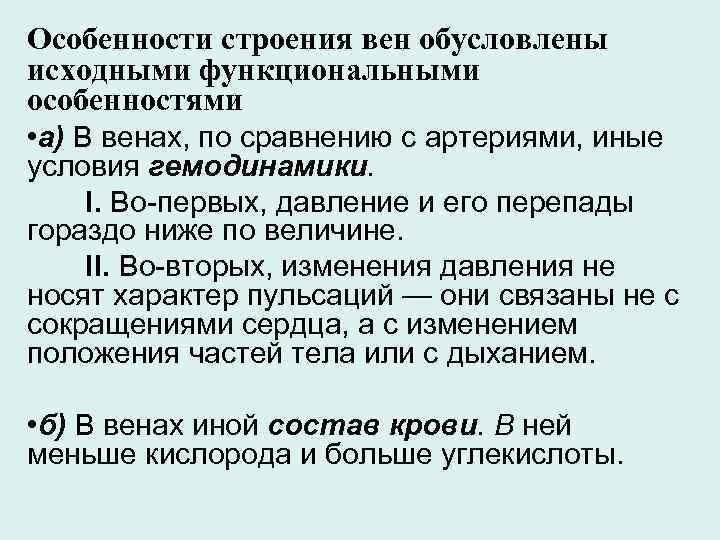

Особенности строения вен обусловлены исходными функциональными особенностями • а) В венах, по сравнению с артериями, иные условия гемодинамики. I. Во-первых, давление и его перепады гораздо ниже по величине. II. Во-вторых, изменения давления не носят характер пульсаций — они связаны не с сокращениями сердца, а с изменением положения частей тела или с дыханием. • б) В венах иной состав крови. В ней меньше кислорода и больше углекислоты.